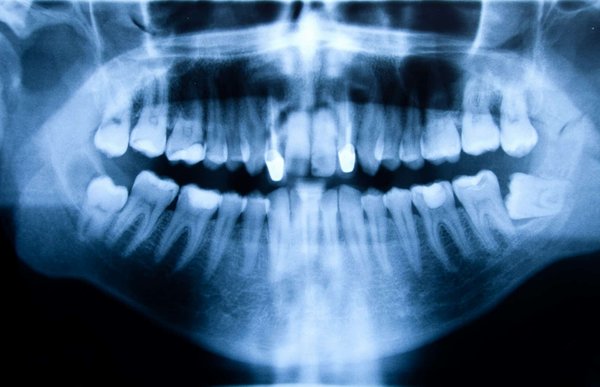

From the start, the significance of oral health for maintaining the overall wellness of an individual has been emphasized by health professionals. Yet, it is often overlooked in the athletic community...